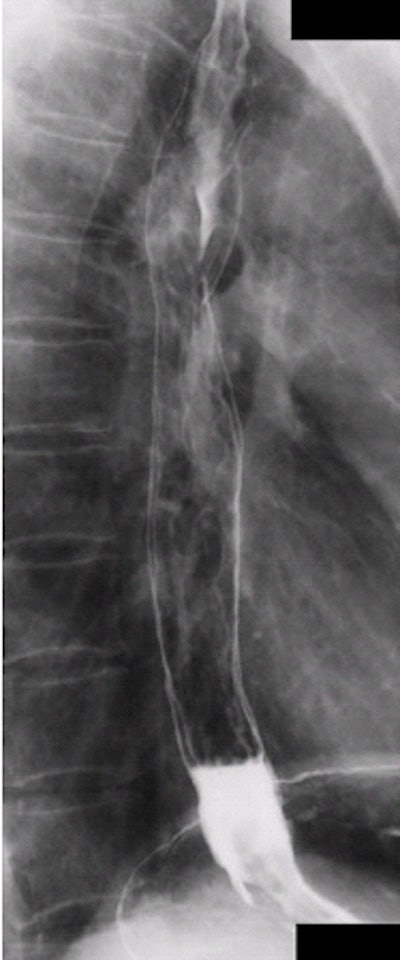

| Lateral esophagus, single-contrast study. Image courtesy of Dr. Naveed Ahmad. |

| A PA esophagus single-contrast study showing a good esophagram. Image courtesy of Dr. Naveed Ahmad. |

- The esophagus should be clearly demonstrated from the lower part of the neck to its entrance into the stomach.

- Technical factors should be adequate for penetration of the barium.

- On an AP or PA projection, the esophagus should be clearly demonstrated through the superimposed thoracic vertebrae.

- No rotation of the patient should be seen on an AP or PA projection.

- On a lateral projection the esophagus is demonstrated between the vertebrae. The heart and ribs posterior to the vertebrae are superimposed to show that the patient was not rotated.

- On an oblique projection the esophagus is demonstrated between the vertebrae and the heart.

- The patient’s arm should not interfere with visualization of the proximal esophagus.